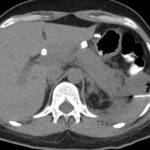

Caso 4

Paciente masculino de 35 años de edad, con antecedentes de tabaquismo, etilismo, consumo de sustancias psicoactivas. Ingresa al hospital de Sanatorio Franchin el 24 de mayo de 2024, donde se constata hipoglucemia severa con buena respuesta al glucosado hipertónico endovenoso. Al examen físico con la típica tríada de Whipple, dado por síntomas neuroglucopénicos de alteración del estado de conciencia, glucemia de 25 mg/dl y alivio sintomático después de la administración de glucosa. El paciente recupera el estado de conciencia y refiere dolor abdominal a nivel de epigastrio, por lo que se le realiza ecografía abdominal, donde se evidencia lesión nodular hipoecogénica en cuerpo del páncreas. Por esta razón se pasa al paciente a tomografía, donde se constata una formación nodular a nivel del cuerpo del páncreas, que presenta un ávido realce en fase arterial con homogeneización de la lesión en tiempo tardío.